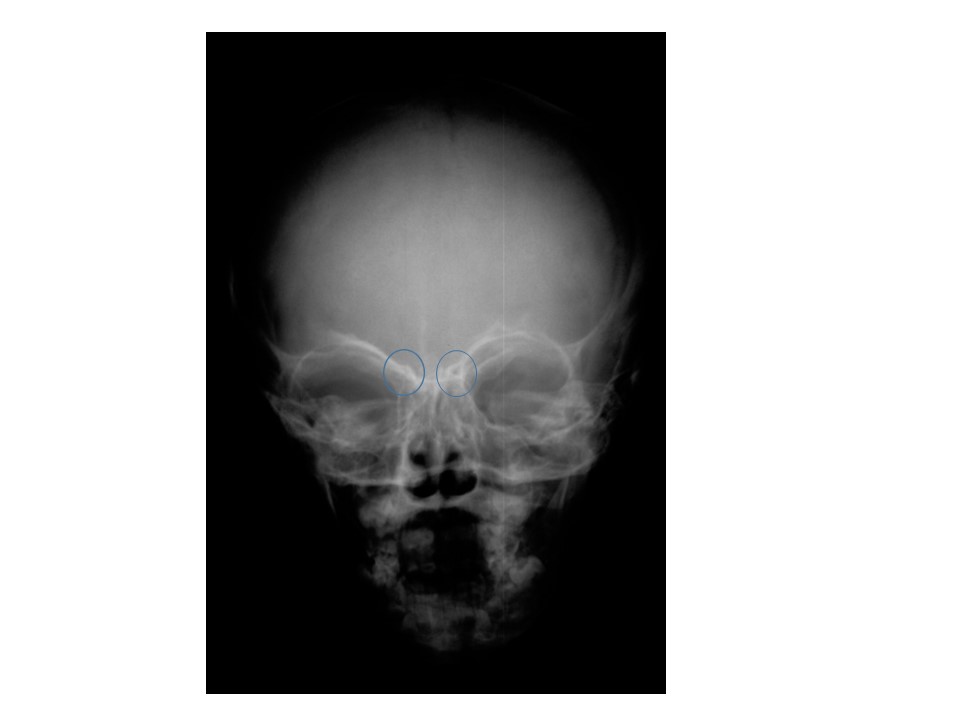

Juvenile skull showing stage one of frontal sinus development.

Frontal sinuses begin to appear under X-ray around ages 6 to 8. North Carolina State University

The study described four phases of frontal sinus development of the skull using X-ray images of 392 juveniles: complete lack of frontal sinus development (ages six and under), development of two small, kidney-bean-shaped areas around the front of the forehead (six to eight), initial stages with two cavities that touch but don’t merge (seven to ten), and fully-formed merging frontal sinuses (twelve to eighteen).